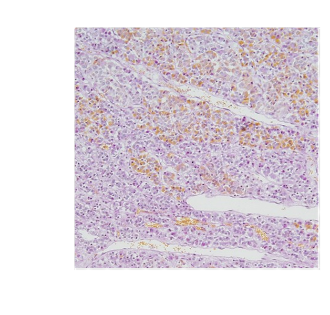

high magnification of pituitary gland

orange dots - rbc